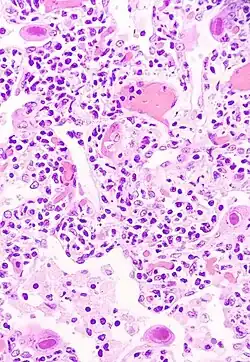

Die Gattung Cytomegalovirus (deutsch auch Zytomegalievirus) umfasst derzeit sechs klassifizierte Virusspezien aus der Familie Orthoherpesviridae. Der Gattungsname entstammt der früheren Typspezies, dem Humanen Cytomegalievirus, das bei einer Infektion zu mikroskopisch charakteristischen, vergrößerten Zellen führen kann. Dabei kommt es zu einer Volumenzunahme des Zellplasmas und zu typischen Einschlusskörperchen im Plasma wie auch im Zellkern. Innerhalb der Subfamilie der Betaherpesvirinae zeichnen sich die Mitglieder der Gattung Cytomegalovirus durch ein besonders großes Virusgenom von mehr als 200.000 Basenpaaren aus.